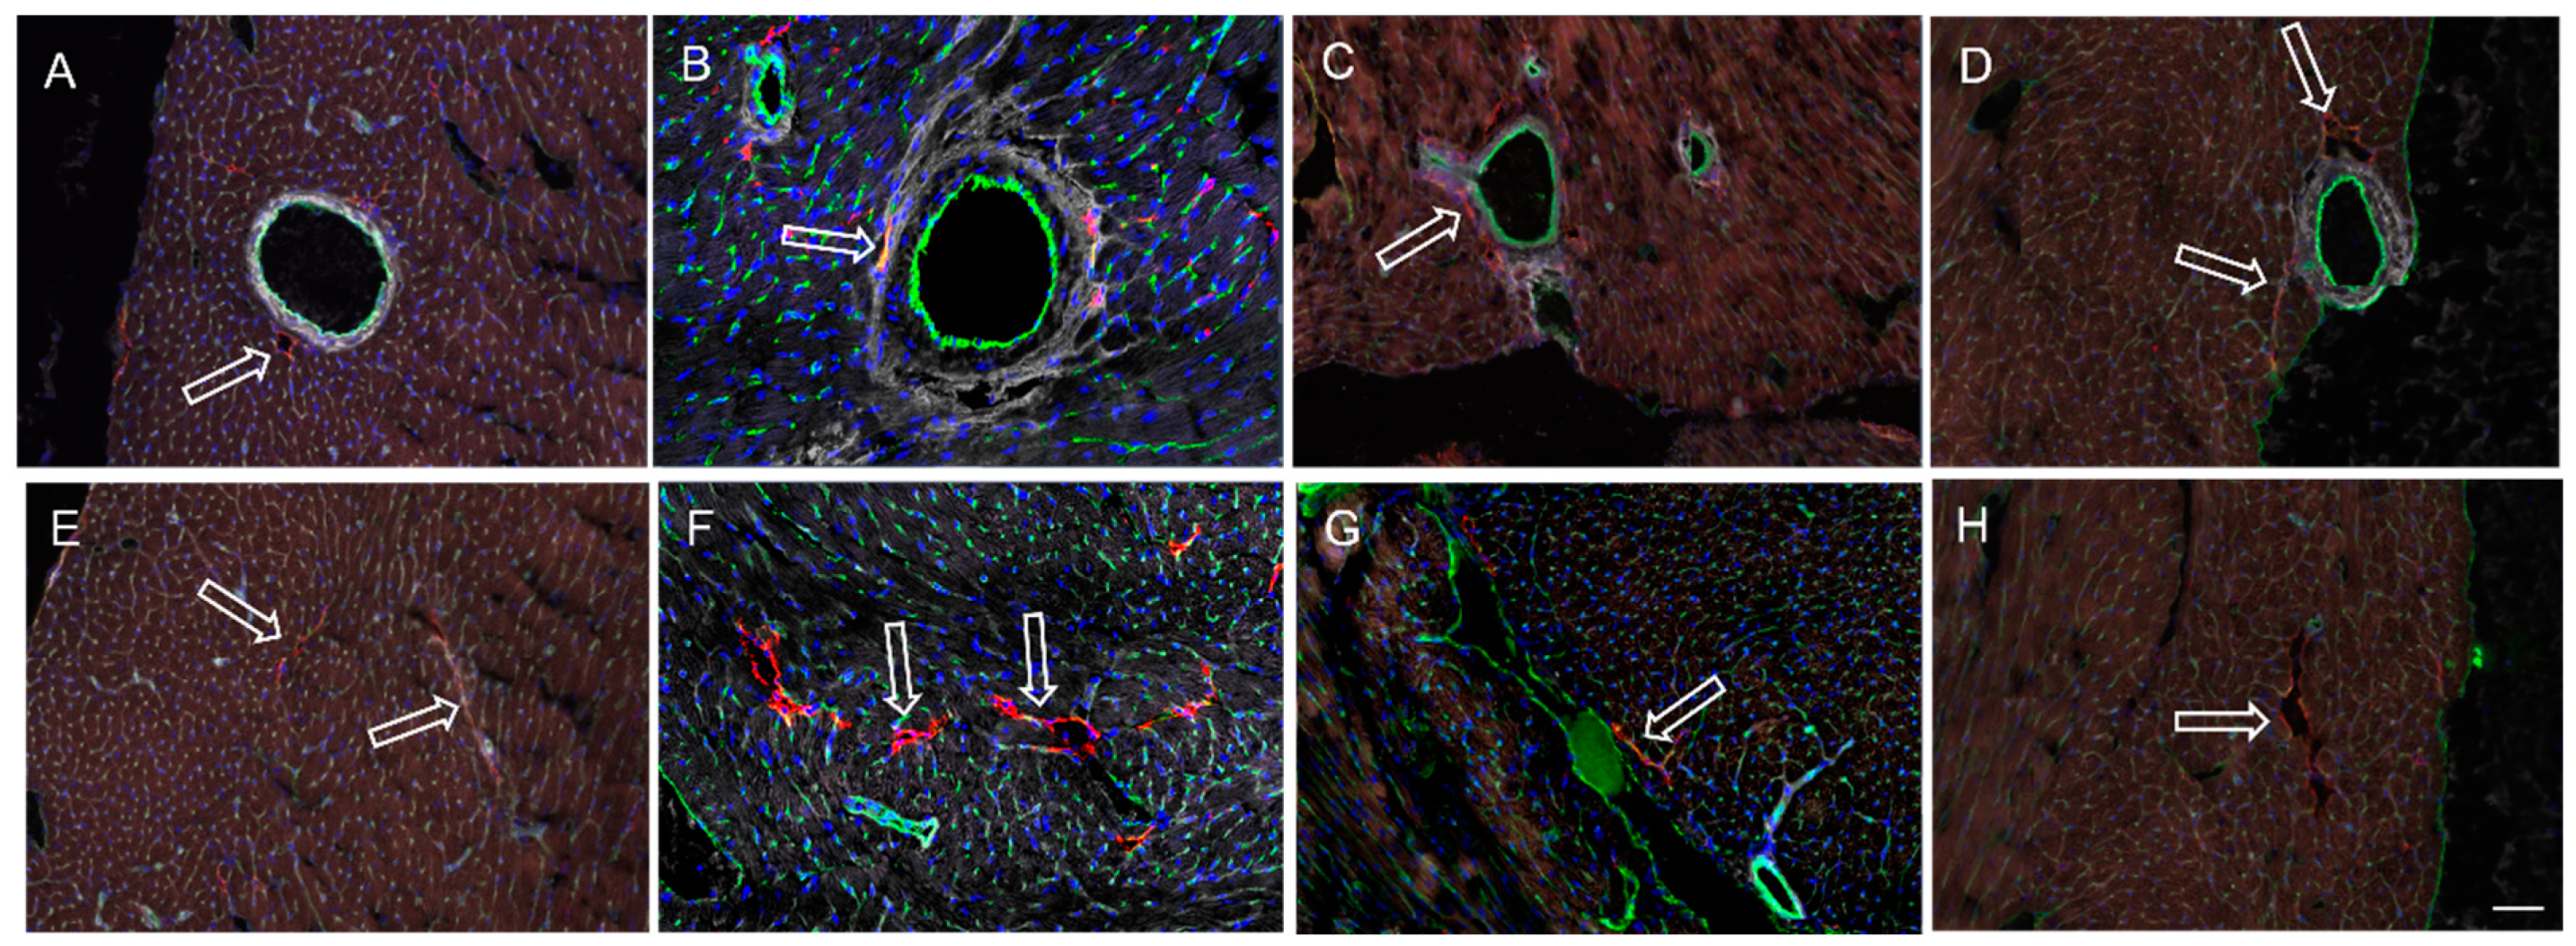

2.4. Confocal Microscopic Evaluation of Cardiac Lymphatics

3.3. Cardiac LyV Density and Structural Remodeling